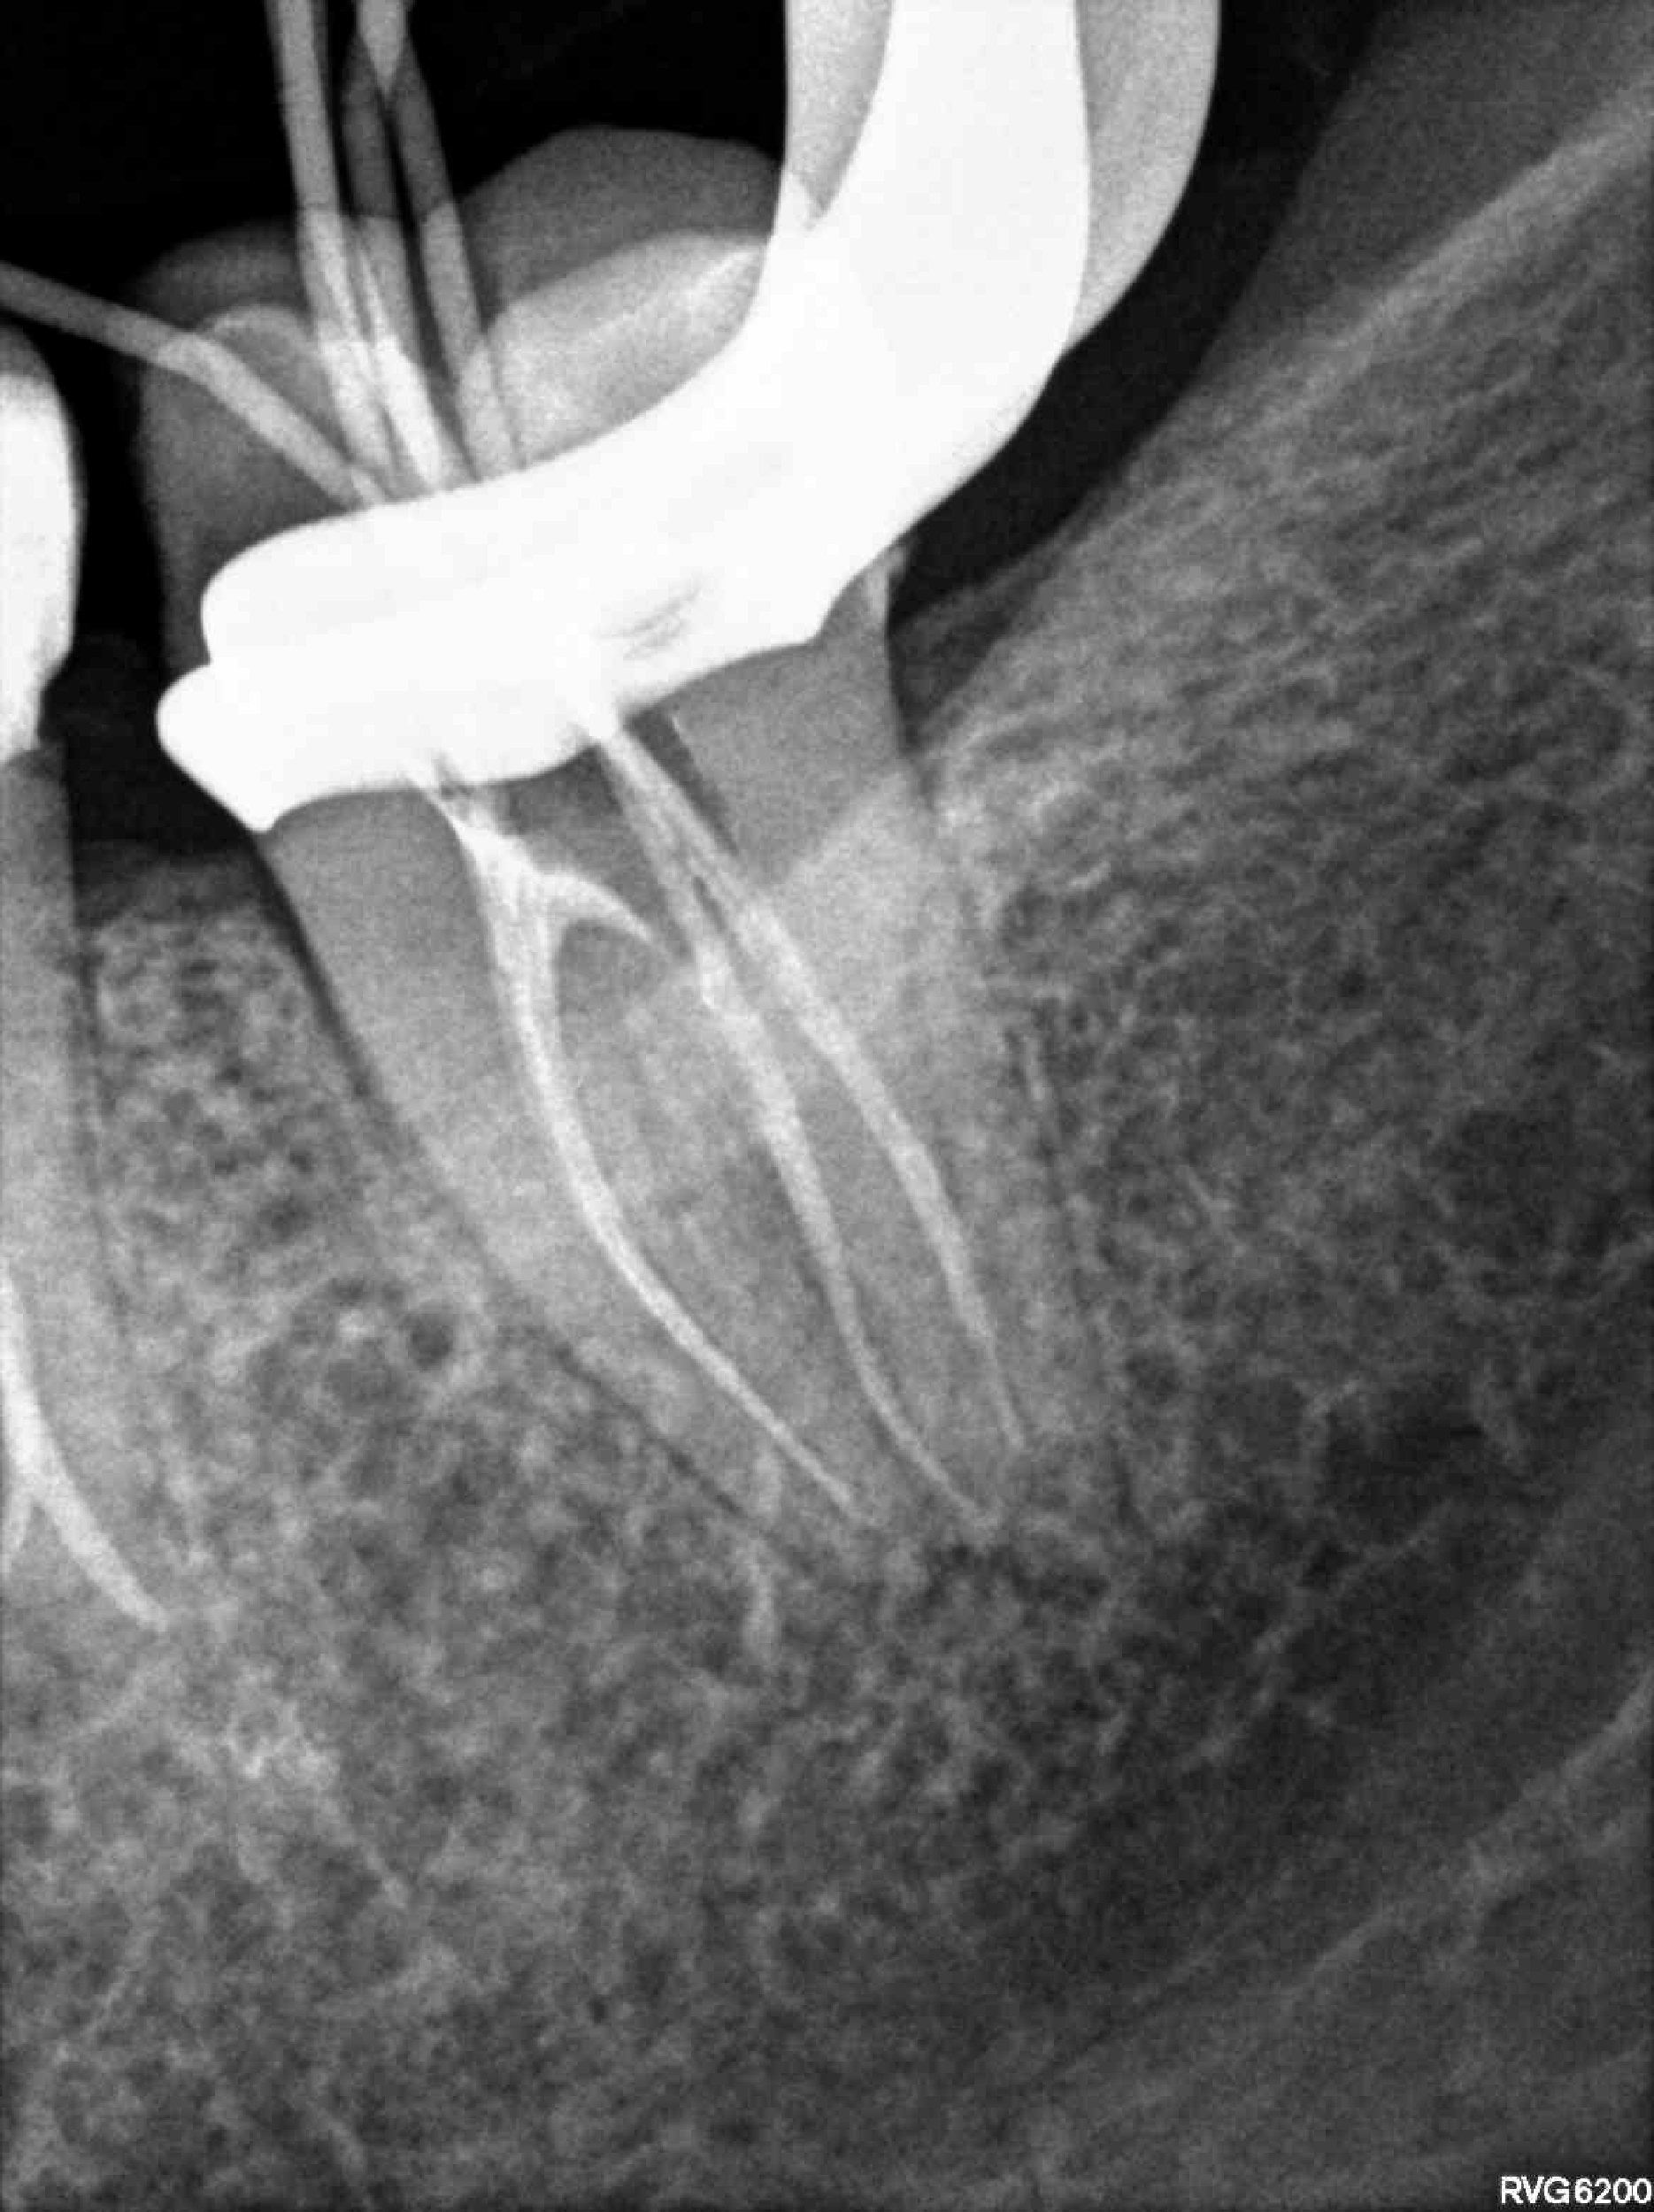

Categoría Endodoncia

Radiografías

Imágenes del tratamiento